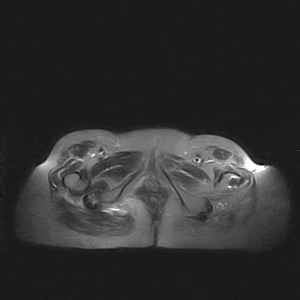

标题: MRI2691:读片病例2

我帮传的没看到病史!!!

图像太差了 1、右侧臀肌旁脓肿? 建议增强 2、左侧股骨头坏死并半脱位

1、左侧股骨头坏死并髋关节半脱位;

2、右侧臀肌感染,(可能褥疮所致)